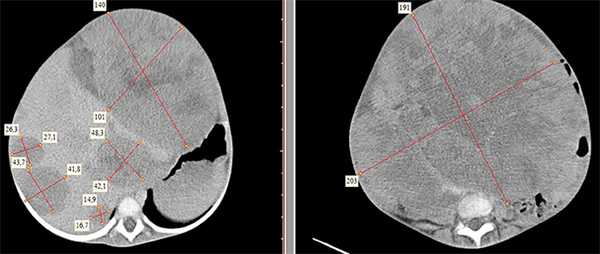

Результаты исследования: размеры плода пропорциональные, соответствуют менструальному сроку беременности. При эхокардиографии особенностей строения сердца у плода не выявлено. При оценке органов мочевыделительной системы обнаружено следующее: правая почка плода нормальных размеров и структуры. Левая почка увеличена до размеров 53х38х46 мм при 95-м процентиле нормативных для срока значений 43х24х23 мм [4] (рис. 1). В структуре почки, преимущественно в верхнем и среднем сегментах, определяется округлое образование без четких контуров, средней эхогенности, приблизительные размеры его 50х35х35 мм. При цветовом допплеровском картировании в образовании визуализируется обширная сосудистая сеть. При допплерометрии индексы сосудистой резистентности (рис. 2) в разных участках образования варьируют в широких пределах (от 0,49 до 0,77).

Рис. 1. Почки плода в режиме 2D. Видна разница в эхографической структуре. Границы почек обозначены стрелками.

Рис. 2. Режим цветового допплеровского картирования. Хорошо видны различия в характере васкуляризации нормальной почки и контрлатеральной пораженной почки.

В представленном клиническом наблюдении диагноз опухоли почки был поставлен нами практически сразу и не вызывал сомнения, поскольку стандартный протокол ультразвукового скринингового исследования во II и III триместрах беременности требует описания почек и мочевого пузыря. Почки оцениваются в поперечном и продольном сечениях с использованием при необходимости цветового допплеровского картирования (рис. 3, а, б). В данном случае почки плода располагались в типичном месте, но обращали на себя внимание значительная разница в размерах и необычная структура одной из почек (см. рис. 1). В 2D режиме границы опухоли четко не визуализировались, но при использовании технологии VCI (объемное контрастное изображение) можно было более точно определить ее контуры (рис. 4).

а) Поперечное сканирование. Переднезадний размер почек обозначен стрелками.